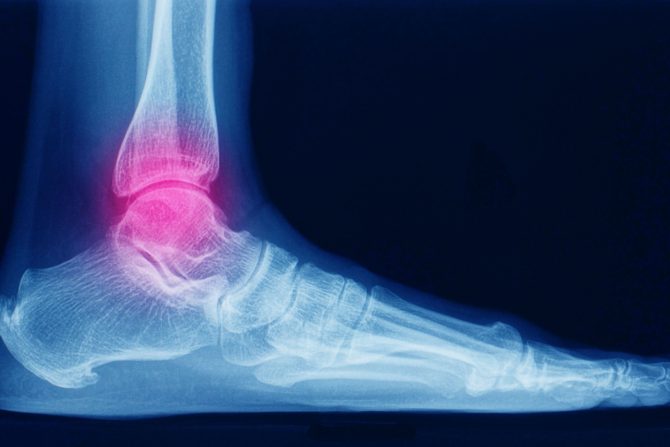

Oslanjanje na skočni zglob, poznato i kao "nošenje težine", dozvoljeno je posle određenog vremena, neophodnog za oporavak. Ne postoje utvrđene smernice koje treba slediti kada pacijenti mogu da se svom težinom oslanjanju na slomljene kosti skočnog zgloba, kažu naučnici, i podsećaju da su prošla istraživanja imala neke oprečne rezultate.

Nova studija istraživača sa University of Missouri School of Medicine ispitivala je kada zdravi pacijenti mogu da se oslanjaju na skočni zglob koji je operisan zbog preloma. Otkrili su da je nakon tri nedelje od hirurškog tretmana bezbedno osloniti se svom težinom na zglob, a celokupna studija objavljena je u Journal of Foot and Ankle Surgery.

Istraživači University of Missouri School of Medicine sproveli su sopstvenu studiju, analizirajući  rezultate 233 pacijenta svrstavajući ih u grupe na osnovu toga koliko dugo nisu koristili skočni zglob. Naučnici ističu da nisu otkrili ništa što bi ukazivalo da je rizik od komplikacija veći kod pacijenata koji nedugo posle operacije stanu na nogu.

- Svrha ove studije bila je da se ispita da li je prevremeno oslanjanje na skočni zglob nakon preloma bilo bezbedno. Prevremeno nošenje težine može da pomogne da se ubrza oporavak pacijenta sprečavanjem dekondicioniranja mišića, poboljšanjem opsega pokreta zglobova i omogući što brže sticanje samostalnosti čoveka da sam hoda - objašnjava autor studije dr Kyle Schweser, ortopedski hirurg i šef odeljenja za stopala i skočni zglob na MU Health Care.